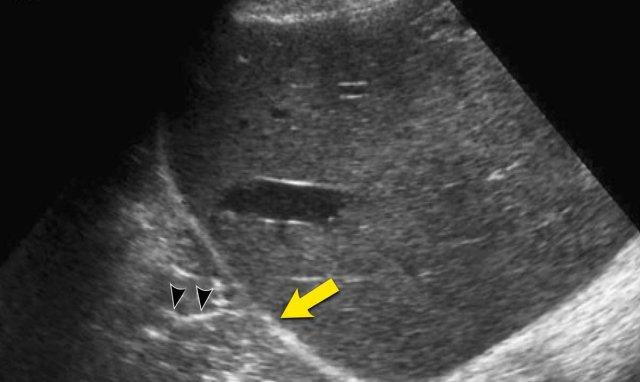

Bé trai 8 tuổi bị viêm phổi với biểu hiện lâm sàng giống viêm ruột thừa.

Siêu âm qua gan phát hiện vùng đông đặc ở thùy dưới phổi phải (mũi tên) kèm theo hình ảnh phế quản đồ khí (đầu mũi tên).

Ruột thừa bình thường (không hiển thị).

Các hình ảnh này thuộc về bệnh nhân nữ 47 tuổi bị viêm phổi, với biểu hiện lâm sàng giống viêm túi mật.

Siêu âm qua gan phát hiện tràn dịch màng phổi bên phải (mũi tên).

Túi mật có hình ảnh bình thường (không hiển thị).

Siêu âm qua khoang liên sườn cho thấy vùng đông đặc phổi kèm hình ảnh phế quản đồ khí (đầu mũi tên).